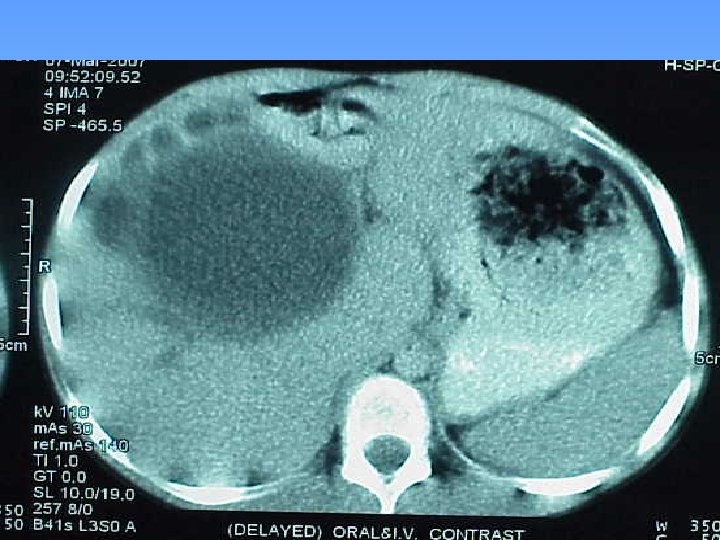

Abdominal CT Scan § A regular lobulated cystic mass in right lobe of liver (120 x 120) without calcification causing dilatation of intra & extra biliary ducts.

MRCP & MRI § Huge thicked wall cystic mass (140 x 120 mm), at the portahepatis that seems connected to biliary tree and gall bladder, resulted in severe dilatation of intra hepatic bile ducts and displaced right kidney posteriorly. § Spleen, kidneys, bowel loops and abdominal wall are normal. § Finding could be due to congenital anomalies like choledocal cyst, Duplication cyst, mesenteric cyst and hydatid cyst are in DDx.